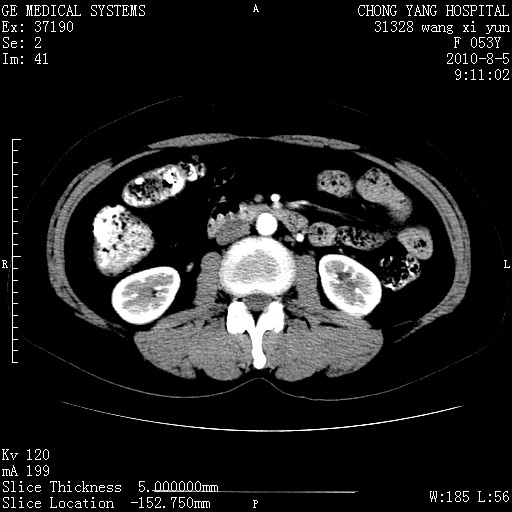

标题: CT28214:F41Y 血尿二十天,建议盆腔平扫加增强。

1)考虑肝左叶胆管细胞癌。2)脂肪肝。